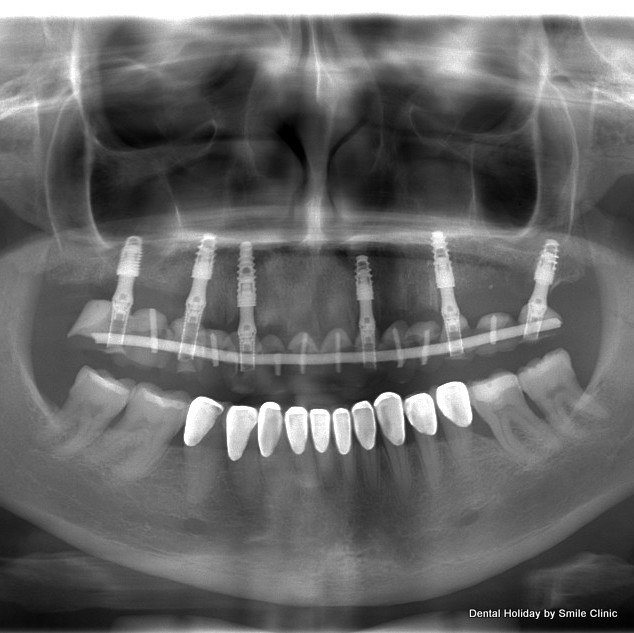

I arrived at the clinic in early December and after X-rays and scans were taken of my mouth by the clinic’s state of the art equipment I had a consultation with Dr. Marek. We sat down together and he clearly pointed out the bone-loss on either side of my upper jaw and confirmed my complaint that I felt the rest of my top teeth were loosening. He marked on the X-ray where he suggested he would place six implants on which to fix a permanent bridge of 14 teeth. I was very glad that he suggested 14 teeth instead of 12 teeth as I have a wide smile and would have been uncomfortable if it looked like my back teeth were missing.